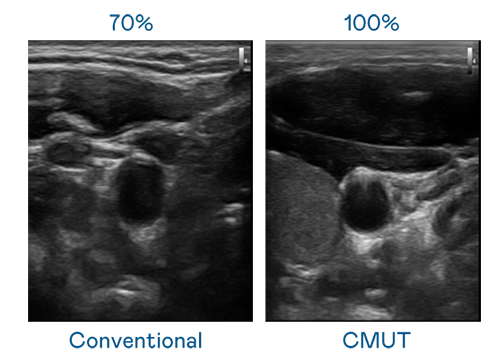

CMUT 技術是一種用電容式微機電元件來產生超音波訊號的技術。與傳統 PZT 壓電式技術相比,CMUT 頻寬增加 30%,更寬頻的超音波訊號讓影像解析度大幅提升,是實現高影像品質醫療超音波掃描、促進精準醫療發展的關鍵技術。

超音波影像的解析度高低,首先取決於探頭能發出的訊號頻寬。w66旗舰厅 CMUT 可提供高清晰的超音波訊號,提供高頻寬、高靈敏度、影像紋理細節更高的超音波影像,協助醫護人員縮短影像判讀時間及利用精準的醫療影像進行診斷。